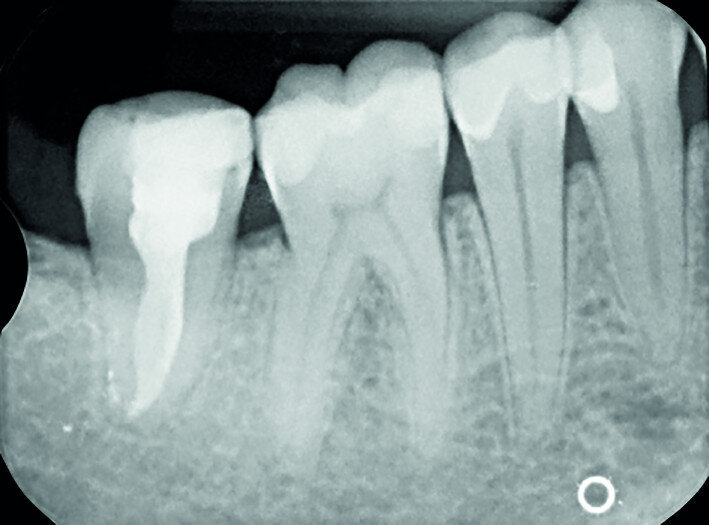

Fig. 16a: Pre-op periapical radiograph.

Fig. 16b: Radiograph at the one-year recall.

Fig. 16c: Radiograph at the 11-year recall.

A right mandibular first molar of a 16-year-old female patient with heavy structural damage was extracted after explanation, informed consent and a mandibular block with 3 per cent mepivacaine. The receiving site was debrided, and the right mandibular third molar was atraumatically extracted, positioned in the alveolus and stabilised with sutures. An antibiotic (amoxicillin/clavulanic acid, 1 g, by mouth twice a day for five days) and a non-steroidal anti-inflammatory drug (ibuprofen, 600 mg, by mouth twice a day for five days) were prescribed, along with rinses with 0.2 per cent chlorhexidine. The sutures were removed after two weeks and the endodontic treatment was performed after two months. The tooth was still in full function after 11 years (Figs. 16a–d).